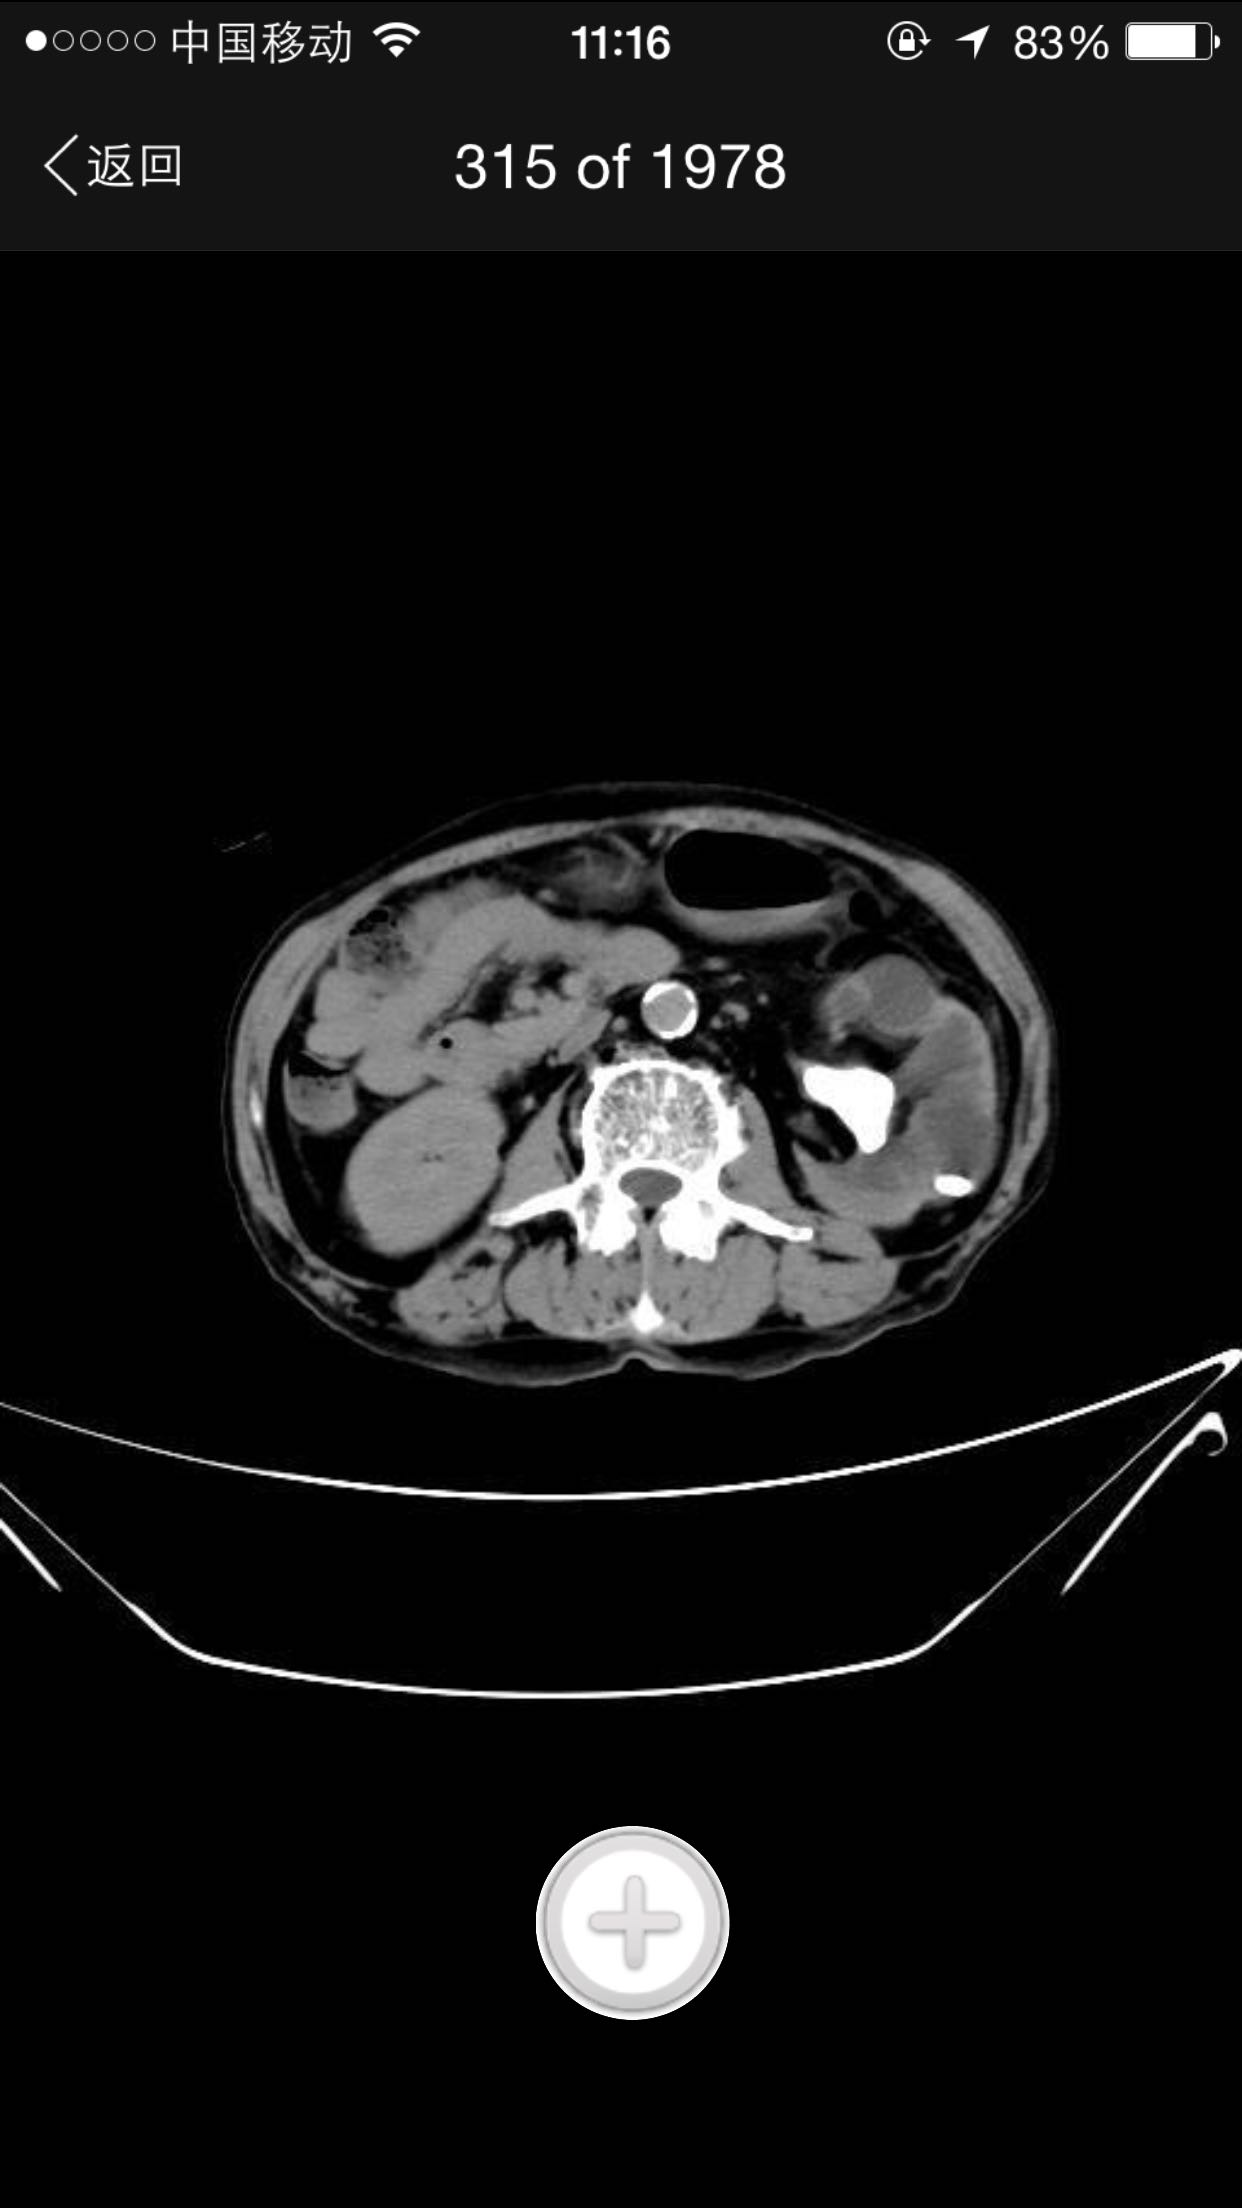

排尿困难,尿潴留入院。诊为前列腺增生症,拟行手术治疗。完善术前检查,泌尿系CT检查发现左肾占位,左肾结石并左肾重度积水,左肾萎缩等。既往患者肺结核病史,服药控制半年余。

查体:腹平软,无压痛及反跳痛,无肾区叩痛,肛诊前列腺明显增大,中央沟消失,无硬结,无压痛。术前强化CT提示左肾癌。

术前诊断:1、左肾癌2、左肾结石3、左肾积水4、左肾萎缩5、前列腺增生6、肺结核 入院后完善检查,拟行TURP,因发现左肾癌,改为先行肾手术。患者左肾癌,同时左肾结石,肾萎缩,决定行根治性肾切除,拟腹腔镜下手术,患者家属不同意,改开放手术,全麻下行根治性左肾切除。术后剖开标本如下图,肿瘤位于肾上极,中间黑色为结石。